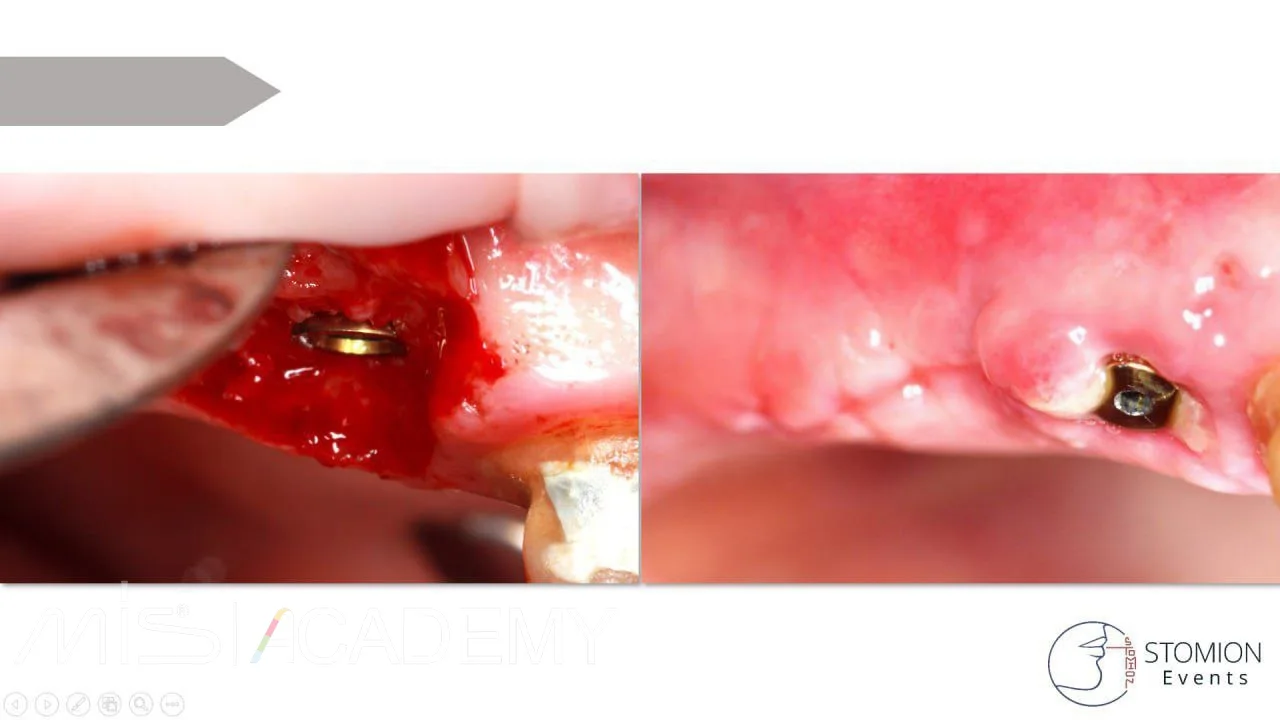

— Установлены имплантаты MIS C1, коннект абатменты,

— На ВЧ вестибулярно — ДСДТ, на НЧ вестибулярно и орально.

— В зазоры лунок уложен Bio-Oss S, сверху A-PRF мембраны в два слоя.